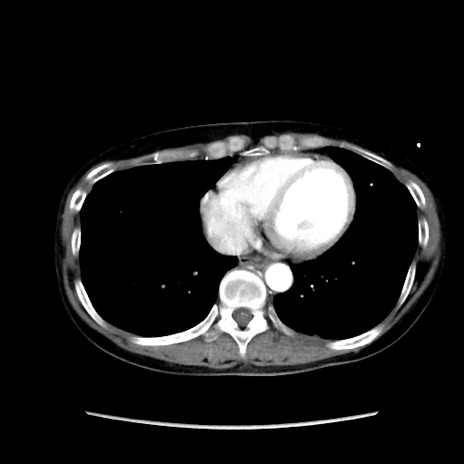

症例32(横断像)

【症例】40歳代 女性

【主訴】上腹部痛、嘔気・嘔吐

【現病歴】約9時間前頃から急に上腹部痛、嘔気、嘔吐が出現。改善しないため救急要請。

【既往歴】子宮頚癌(広汎子宮全摘術、放射線療法)、腸閉塞

【身体所見】腹部:平坦、軟、腸雑音亢進、上腹部を中心に腹部全体に圧痛あり。

【データ】WBC 8400、CRP 0.03